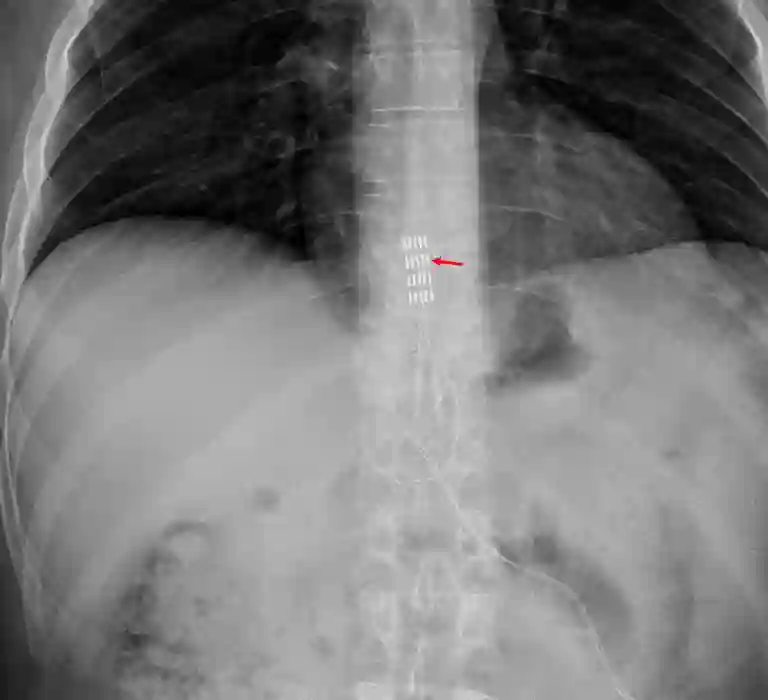

Plattenelektrode

Abbott Penta Plattenelektrode

Darstellung einer Abbott Penta Plattenelektrode im ap Röntgenbild auf Höhe der Brustwirbelsäule.